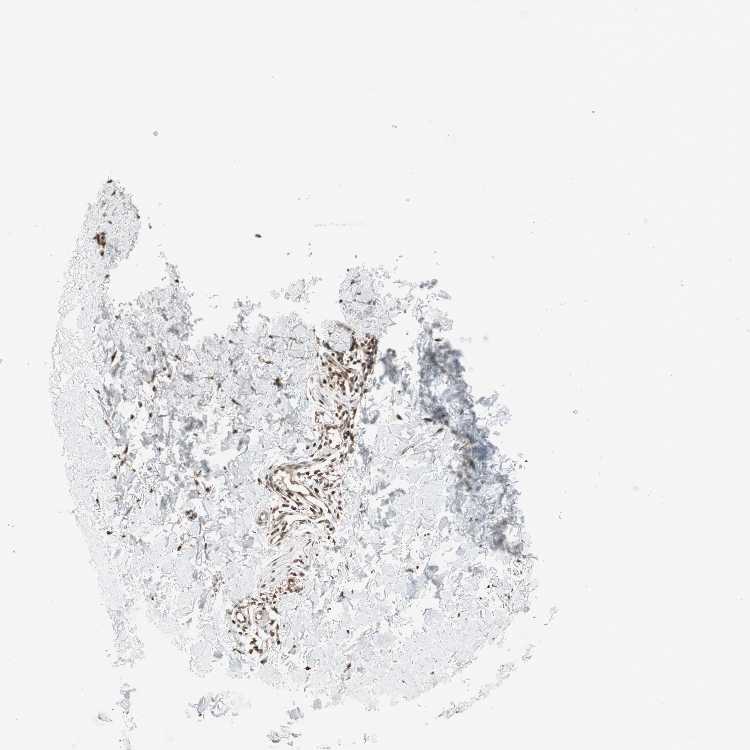

SKIN 1 - Antibody stainingi

Antibody staining in the annotated cell types in the current human tissue is reported as not detected, low, medium, or high, based on conventional immunohistochemistry profiling in selected tissues. This score is based on the combination of the staining intensity and fraction of stained cells.

Each image is clickable and will lead to virtual microscopy that enables deeper exploration of all samples and also displays staining intensity scores, fraction scores and subcellular localization as well as patient and tissue information for each sample.

Antibody HPA005435Antibody CAB020724

Langerhans MediumLow

Fibroblasts MediumLow

Keratinocytes HighLow